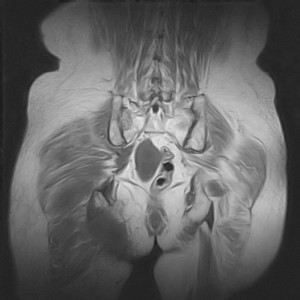

图像太差了 1、右侧臀肌旁脓肿? 建议增强 2、左侧股骨头坏死并半脱位

1、左侧股骨头坏死并髋关节半脱位;

2、右侧臀肌感染,(可能褥疮所致)